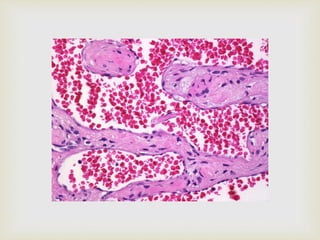

 Cavernous hemangioma

 Large dilated blood sinuses with thin walls showing

endothelial cells

 Sinusoidal spaces are usually filled with blood

 Sometimes lymph vessels may be present

HEMANGIOMA

Histopathology